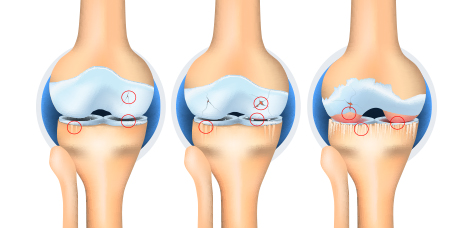

무릎 관절염

슬개골연화증, 관절염 등으로 인해 통증이 발생